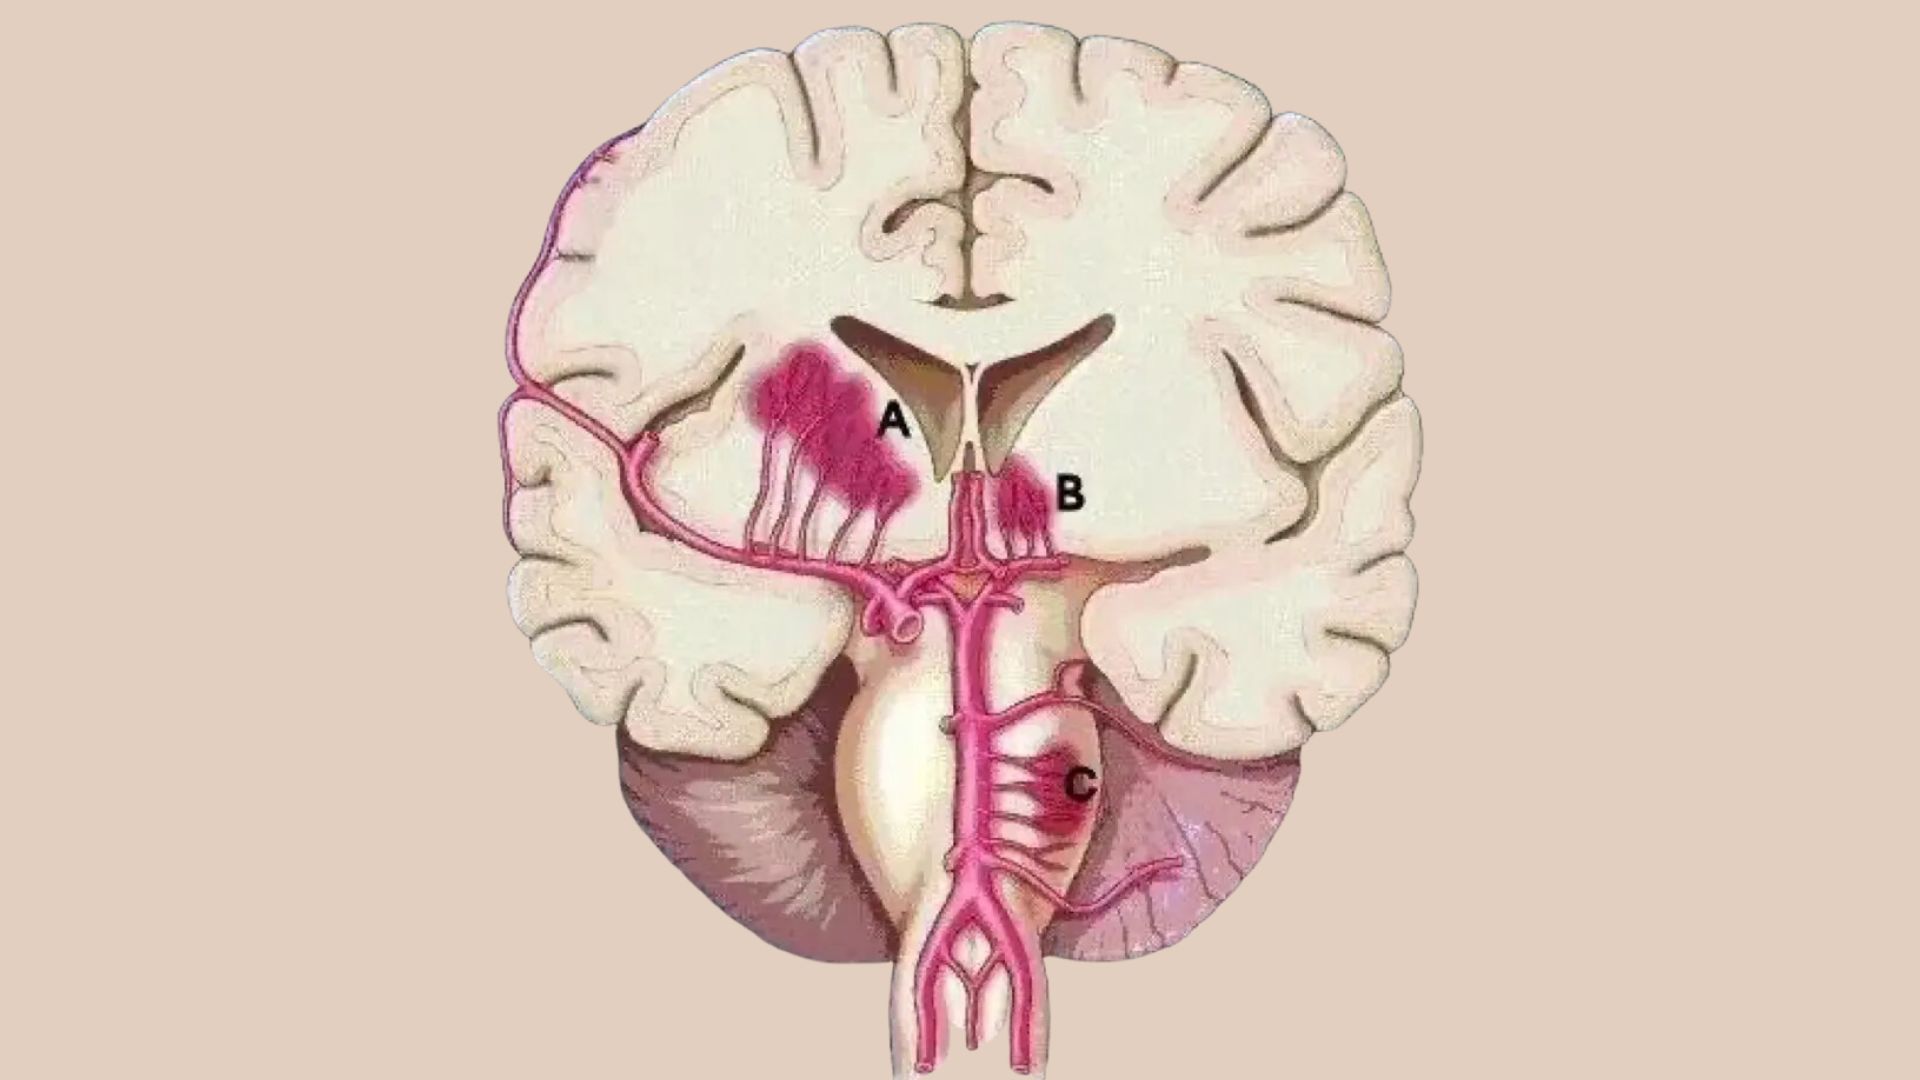

Nhồi máu não lỗ khuyết là những ổ tổn thương nhỏ dưới vỏ có đường kính dưới 15mm do tắc các tiểu động mạch hoặc động mạch xiên (penetrating arteries) là những nhánh tách trực tiếp từ các động mạch não lớn, thường gặp nhất là từ đa giác Willis, động mạch não giữa và động mạch nền.

Các triệu chứng được biểu hiện tùy theo vị trí lỗ khuyết. Phần lớn các trường hợp, bệnh cảnh thường gặp, bao gồm: Bại vận động (liệt nhẹ) đơn thuần nửa người (mặt, tay, chân) là do vị trí lỗ khuyết ở bao trong hay cầu não; đột quỵ cảm giác đơn thuần là vị trí lỗ khuyết ở nhân bụng – bên của đồi thị; bại nửa người, thất điều (vị trí lỗ khuyết ở cầu não); loạn vận ngôn – tay vụng về (… cầu não hay gối của bao trong); bại vận động nửa người với mất ngôn ngữ vận động (… bao trong và tia vành kề bên); liệt giả hành não là nguyên nhân xa phổ biến nhất của nhồi máu nhiều lỗ khuyết và có liên quan các bó vỏ – gai và vỏ hành.

Khu trú lỗ khuyết thường gặp là nhân bào (37%), đồi thị (14%), bao trong (10%), cầu não (36%), vành tia, bao ngoài, bó tháp và các cấu trúc khác của thân não. Thường gặp khoảng 18-40% bệnh nhân trước đó đã bị các cơn thiếu máu não cục bộ tạm thời. Các triệu chứng có thể xuất hiện đột ngột hoặc từ từ, các thiếu hụt thần kinh tiền đình chậm trong 2-3 ngày và xuất hiện xuất huyết nhỏ mà chụp cắt lớp vi tính (CT-scanner chỉ phát hiện được 2/3 trường hợp, còn chụp cộng hưởng từ (MRI) có khả năng chẩn đoán với tỷ lệ cao hơn.